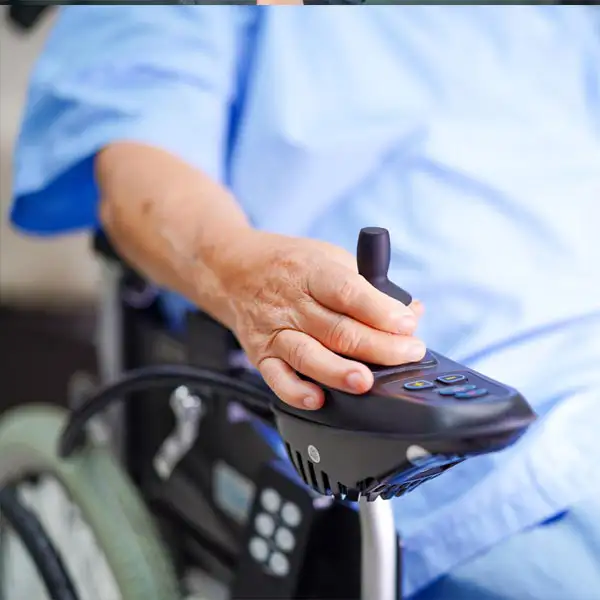

Contamos con la más más alta tecnología en órtesis y protesis, para que te sientras seguro, cómodo y mejorar tu calidad de vida.

La prótesis es una extensión artificial que sustituye a una parte del cuerpo que no existe, ya sea por agenesia o por amputación. De esta forma, se reemplaza la función del miembro que falta para que la persona pueda llevar una vida más cómoda. Pero también sirve para cumplir una función estética.

Por su parte, las órtesis constituyen un apoyo externo que se aplica al cuerpo con el objetivo de cambiar algunos aspectos estructurales o funcionales que tienen que ver con el sistema musculoesquelético. Pero también son muy útiles para economizar energía, alinear o corregir deformidades. Los tipos de órtesis más comunes son los soportes para las rodillas, los pies y el calzado y la espalda tirante.

La principal diferencia entre las órtesis y las prótesis radica en que las prótesis reemplazan y las órtesis complementan o apoyan.